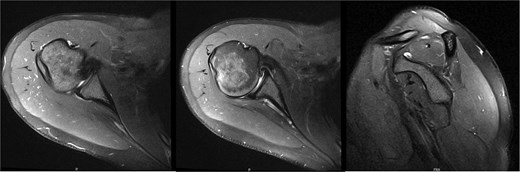

Ten years after initial presentation, the patient returned with increased right shoulder pain after overhead injury at the gym. Her exam included a positive O’Brien’s test, and external rotation weakness. Interval EMG was normal; MRI demonstrated mild supraspinatus tendinosis, and infraspinatus atrophy with unchanged fatty infiltration (Fig. 6). The patient’s pain was hypothesized to be due to infraspinatus atrophy and overuse of other rotator cuff musculature. She elected to manage her symptoms with self-directed therapy.

MRI at final follow-up demonstrated mild supraspinatus tendinosis, and infraspinatus atrophy with continued significant fatty infiltration, unchanged from prior imaging.